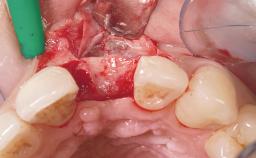

Immediate Flapless Placement of an Implant in a Maxillary Left Central Incisor Site

A 42-year-old female patient was referred to our clinic at the School of Dentistry of the University of São Paulo in November 2004, presenting a deficient restoration in the upper left central incisor. The clinical examination revealed no gingival retraction or any signs of gingival inflammation and, therefore, previous periodontal treatment was not considered. The patient presented a high lip line at full smile and a thin tissue biotype. This combination characterized a high-risk situation from an anatomic point of view, which required careful preoperative planning and cautious surgical execution.

Soft Tissue Grafting None

Abutment Type Customized